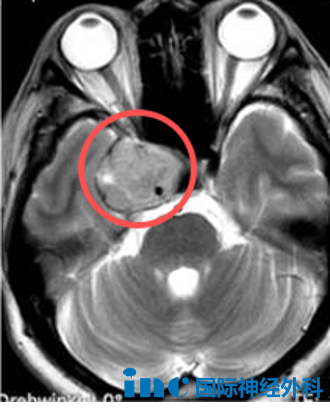

去年8月感冒后出现眼眶胀痛,眼科检查排除眼部病变,鼻科医生建议鼻窦CT排查。意外的是CT扫描显示颅内肿瘤,后续MRI确诊海绵窦区占位,尺寸约2.6 * 3.0 * 4.1cm。此后全家开启求医之路,辗转北京、上海多地仍未能明确肿瘤性质。